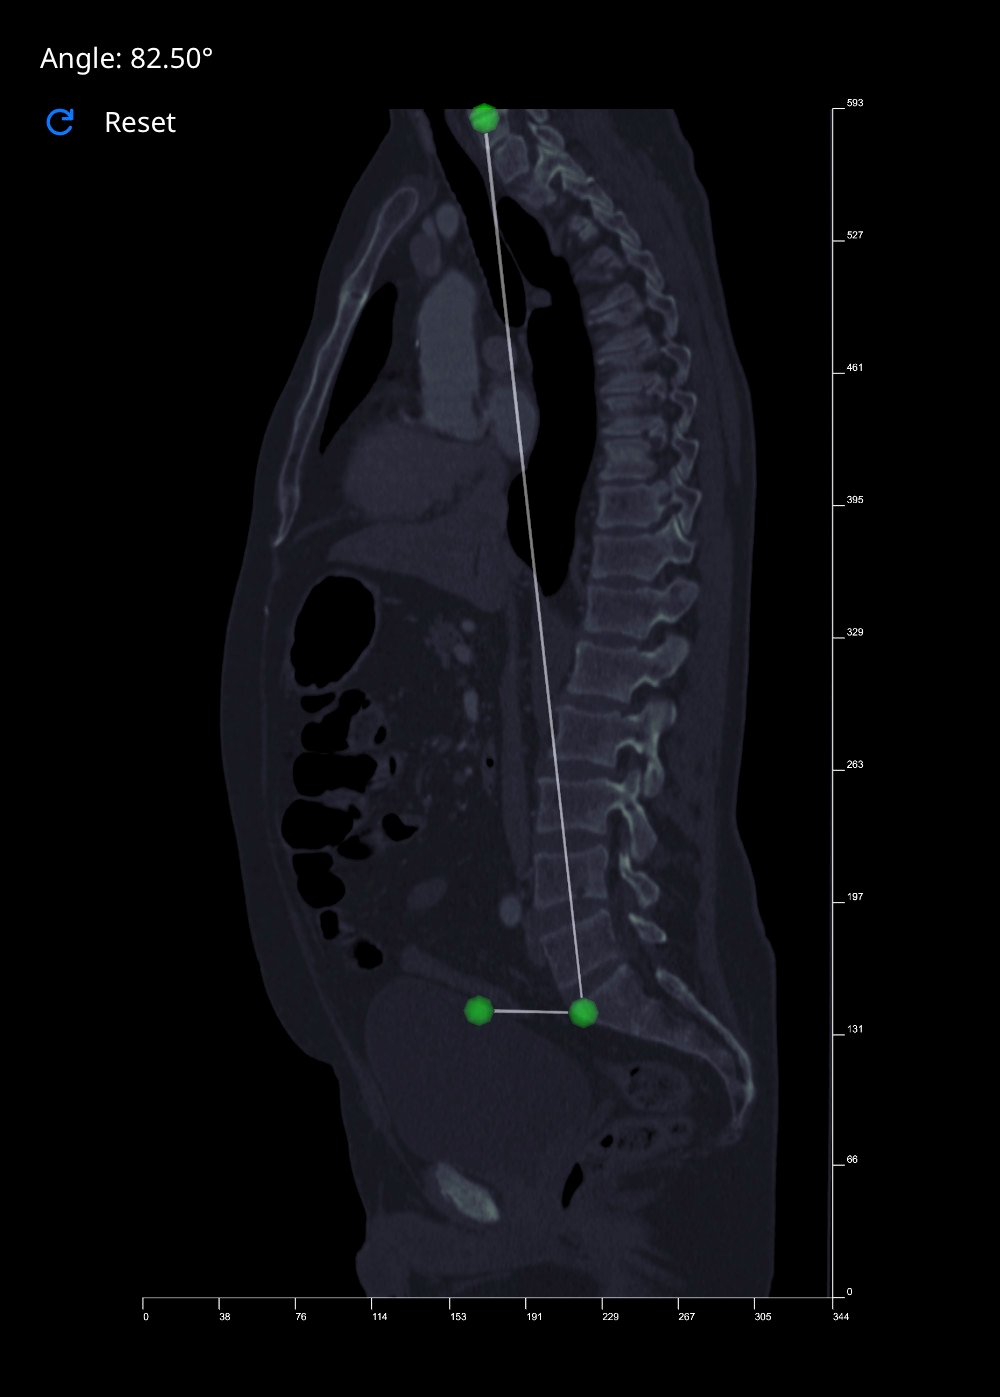

Measure Angle Tool

This tool works by calculating the angle between three points that you place on an image. The second point acts as the vertex, with the first and third acting as the arms of the angle. Follow the steps below to create an angle measurement:

- Select the 'Measure Angle' button. Vista will reduce the opacity of the image in view by half, to make your placement of points more visible and accurate.

- Move your cursor over the image, and left-click to place a point. As you hover over an image, a blue polygon will follow your cursor, giving you an indication of where your point will be placed. Once selected, the polygon will turn green.

- Repeat this process two more times to create the initial side, vertex and terminal side of the angle.

- Once complete, the 'Angle' label at the top-left of the Rendering Canvas will be updated with the measurement.

If you want to start again, click the Reset button to clear the Angle. When you are done, de-select the 'Measure Angle' button to deacivate this tool.

The left image above shows examples of angle measurements in full-length spine radiographs. The image to the right shows a Spinal Tilt angle measurement taken on a CT Scan in Vista.